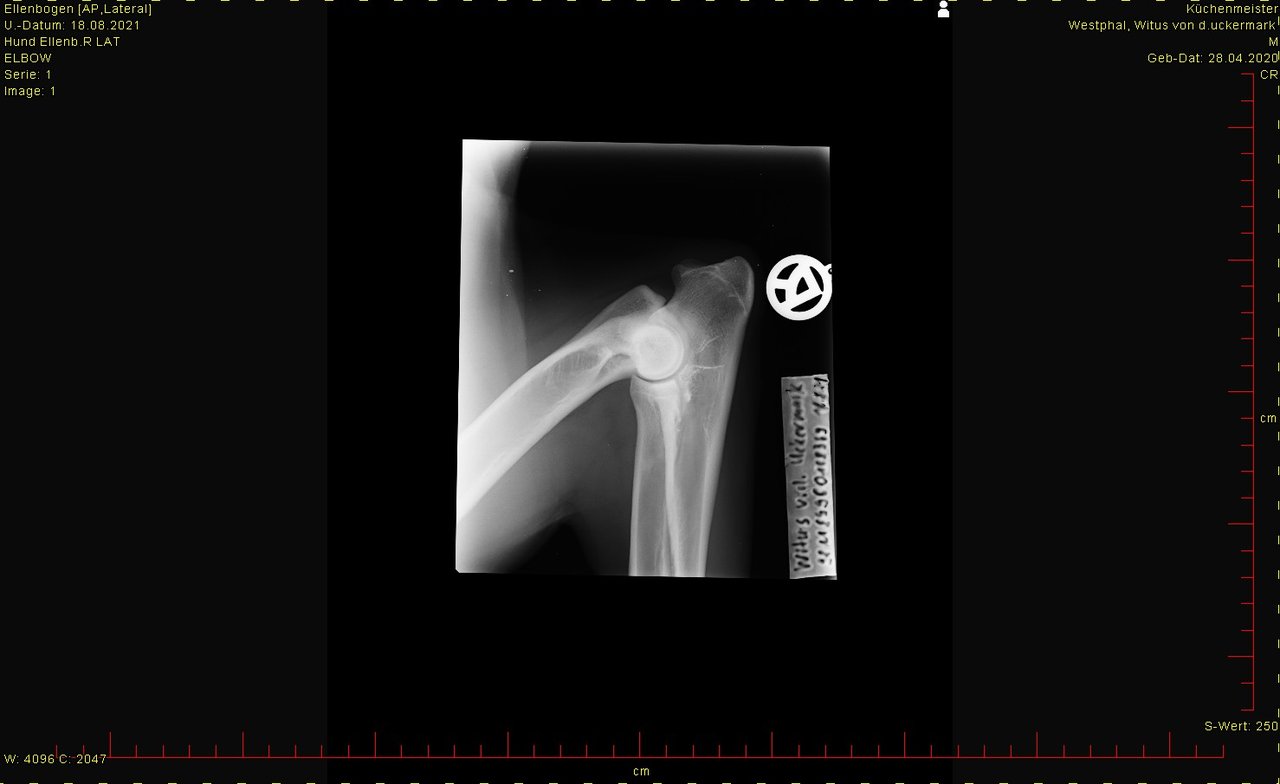

ED hat er nicht, LÜW sah auch ok aus.

Bei den Ellenbogen traue ich mir keine Bewertung zu, finde aber, dass Hüfte und Rücken okay sind